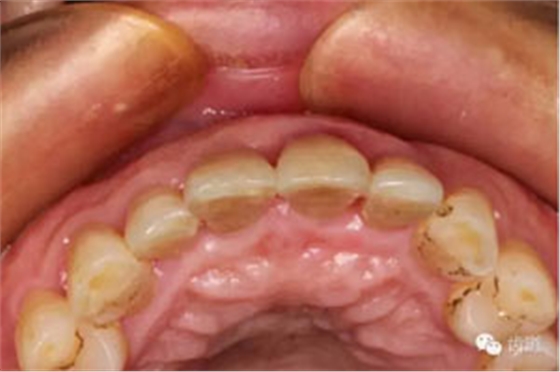

臨床檢查:11,21伸長(zhǎng)1-2mm,松動(dòng)1度,叩(+),21齦緣稍紅腫,唇側(cè)牙槽骨較豐滿,前牙咬合早接觸,中低位笑線,口腔衛(wèi)生一般。

初診照片(合面照)